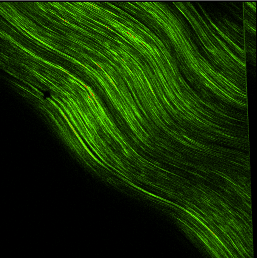

If you were to sustain a hit somewhere on your body with enough force, the point of impact would experience cell death and a micro-hemorrhage of torn capillaries. This trauma would then set up an inflammatory response in the body where vasodilation, clotting mechanisms, and white blood cells would be called upon to help the injured area. The problem is that this chemical chain of events doesn’t just “clean up” the injured area; unfortunately, it also eats/destroys the surrounding healthy tissue. So, if your injury is a small, one-time event, then it’s really no big deal, but, if it happens over and over again on a repetitive basis it becomes a real problem. The area begins to get inflamed; fibers from scar tissue cross bind to other healthy tissue and restrict freedom of motion. There is a loss of capillary beds in the tissue itself. Fluid from the inside of joint or tendon sheaths stops being produced and therefore, the sheaths lose their lubricating effect. Eventually, the healthy tissue is replaced with non-aligned, avascular tissue that has a reduced tensile strength. In other words re-injury and overuse of a joint experiencing tendonitis is likely to result in tendinosis; it’s the way the system is, unfortunately, designed.

The next treatment is very low resistance exercise to keep the joint, above and below, the injury going and the surrounding muscles pumping. This should be done with low to no resistance. The last thing that I like to do is friction massage to the injured tendon. No matter what you do, scar tissue will form secondary to the inflammatory process and we need to align the fibers (which are usually random) with the longitudinal fibers of the tendon itself for tensile strength down the road. If we don’t, a weak point will form in the tendon and, when stressed again, it will more than likely fail meaning we will start again, from the beginning. Friction massage is a “dig and roll” motion at 90 degrees, perpendicular to the long axis of the tendon working from origin to the insertion on the muscle. Start out easy and gradually, over days, increase the pressure. 3-4 x per day x 5-10 min is enough. A recap of phase one is: Fix your cause. Ice. NSAIDS, if you are able. Low-load exercise. Friction massage.